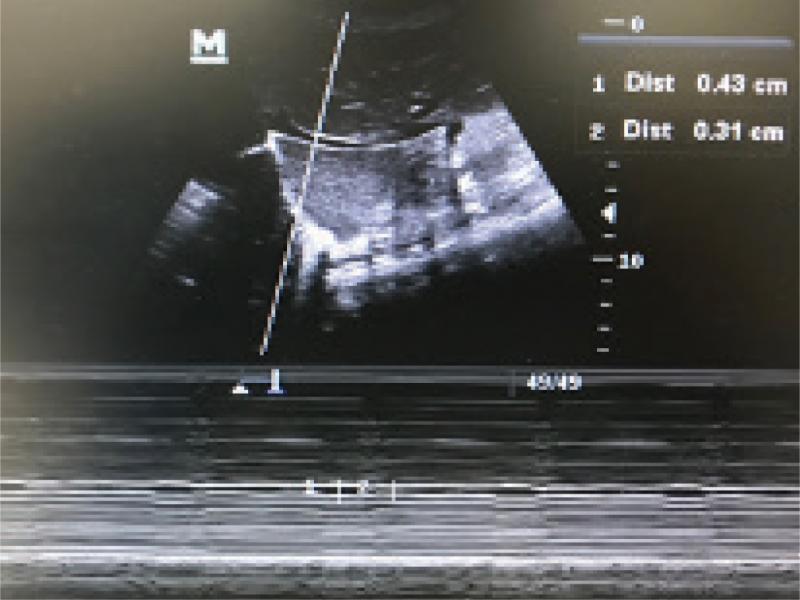

Fig. 2.